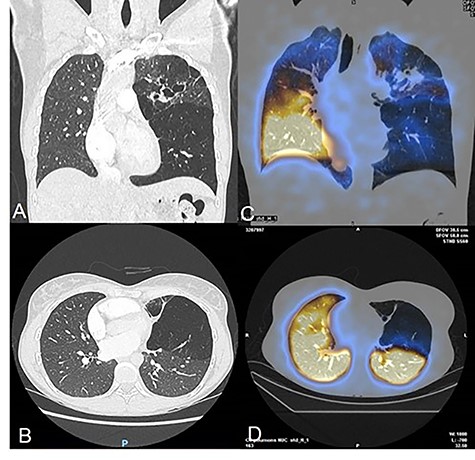

More precisely, the contrast enhanced CT showed a partial stenosis of the upper division segmental bronchus of the left upper lobe, and an atresia of the anterior segmental and the lingular bronchus associated with distal bronchiectasis and superinfection signs (Fig. 1). The left lower lobe presented BA at the level of a supernumerary paracardiac bronchus and an anterobasal segmental bronchus associated with voluminous pulmonary bullae. Some anatomical vascular variations, such as common venous trunk, and a common arterial trunk for the anterior segment of the upper division and the lingula were identified. The right lung did not present anomalies. The ventilation perfusion scintigraphy showed left hypoperfusion corresponding to the left upper lobe (7% of total lung function). After multidisciplinary meeting surgical treatment was proposed.

(A–B) Chest CT-scan showing the complex congenital malformation with destruction of the left superior lobe with bronchiectasis and a voluminous bulla of the left lower lobe. (C–D) Perfusion scintigraphy revealing no perfusion of the left upper lobe and bulla of the left lower.